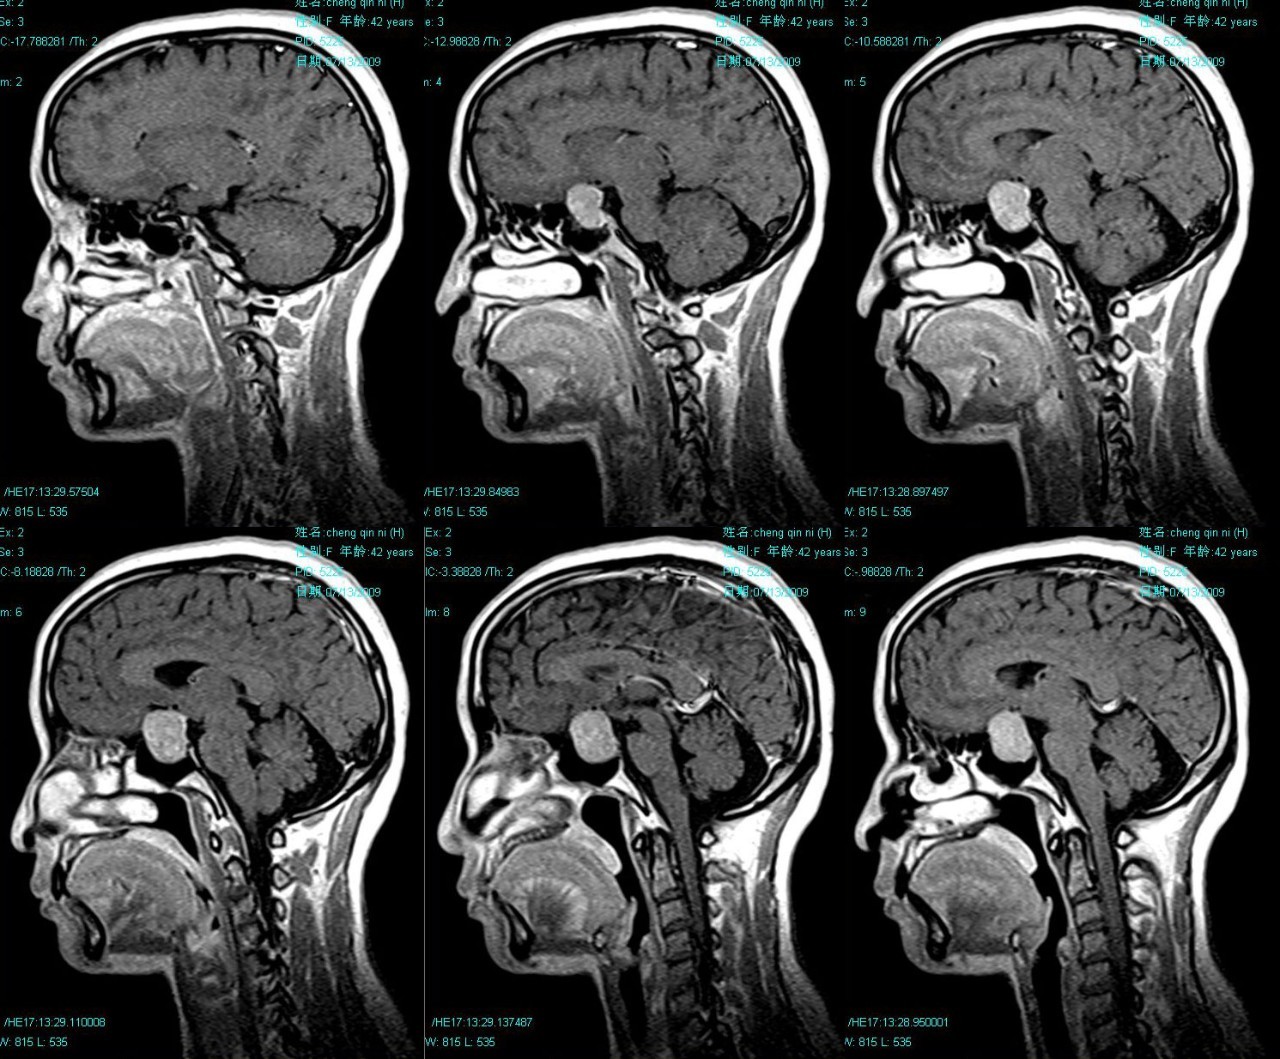

五、临床方法分辨T1像和T2像

T1像

脑脊液CSF是黑色的(黑色只是相对的,大脑中的空气和头骨都是黑色的)。

最外层的白色不是头骨,而是头皮脂肪。在外侧的白色和灰质中间夹的才是头骨。

T1像的灰质相对白质来说暗一些,白质较亮。

T2像

脑脊液CSF是白色的,而灰质比白质更亮一些。

T2-weighed FLAIR像。

和T2像在成像机理上和T2-weighed是差不多的,在灰质和白质的呈现上一样:灰质较亮,白质较暗。不同的是脑脊液CSF表现出了相反的颜色——黑色。

DWI弥散像

主要用来测量水分子的弥散。相对前面的结构像扫描地比较快,大概10分钟可能扫描100次,分辨率相对更低。内部颜色对比不明显。

总结:如果CSF是白色就是T2像如果CSF是白色就是T2像

如果CSF是黑色,白质更亮就是T1像;白质更暗的是FLAIR像。